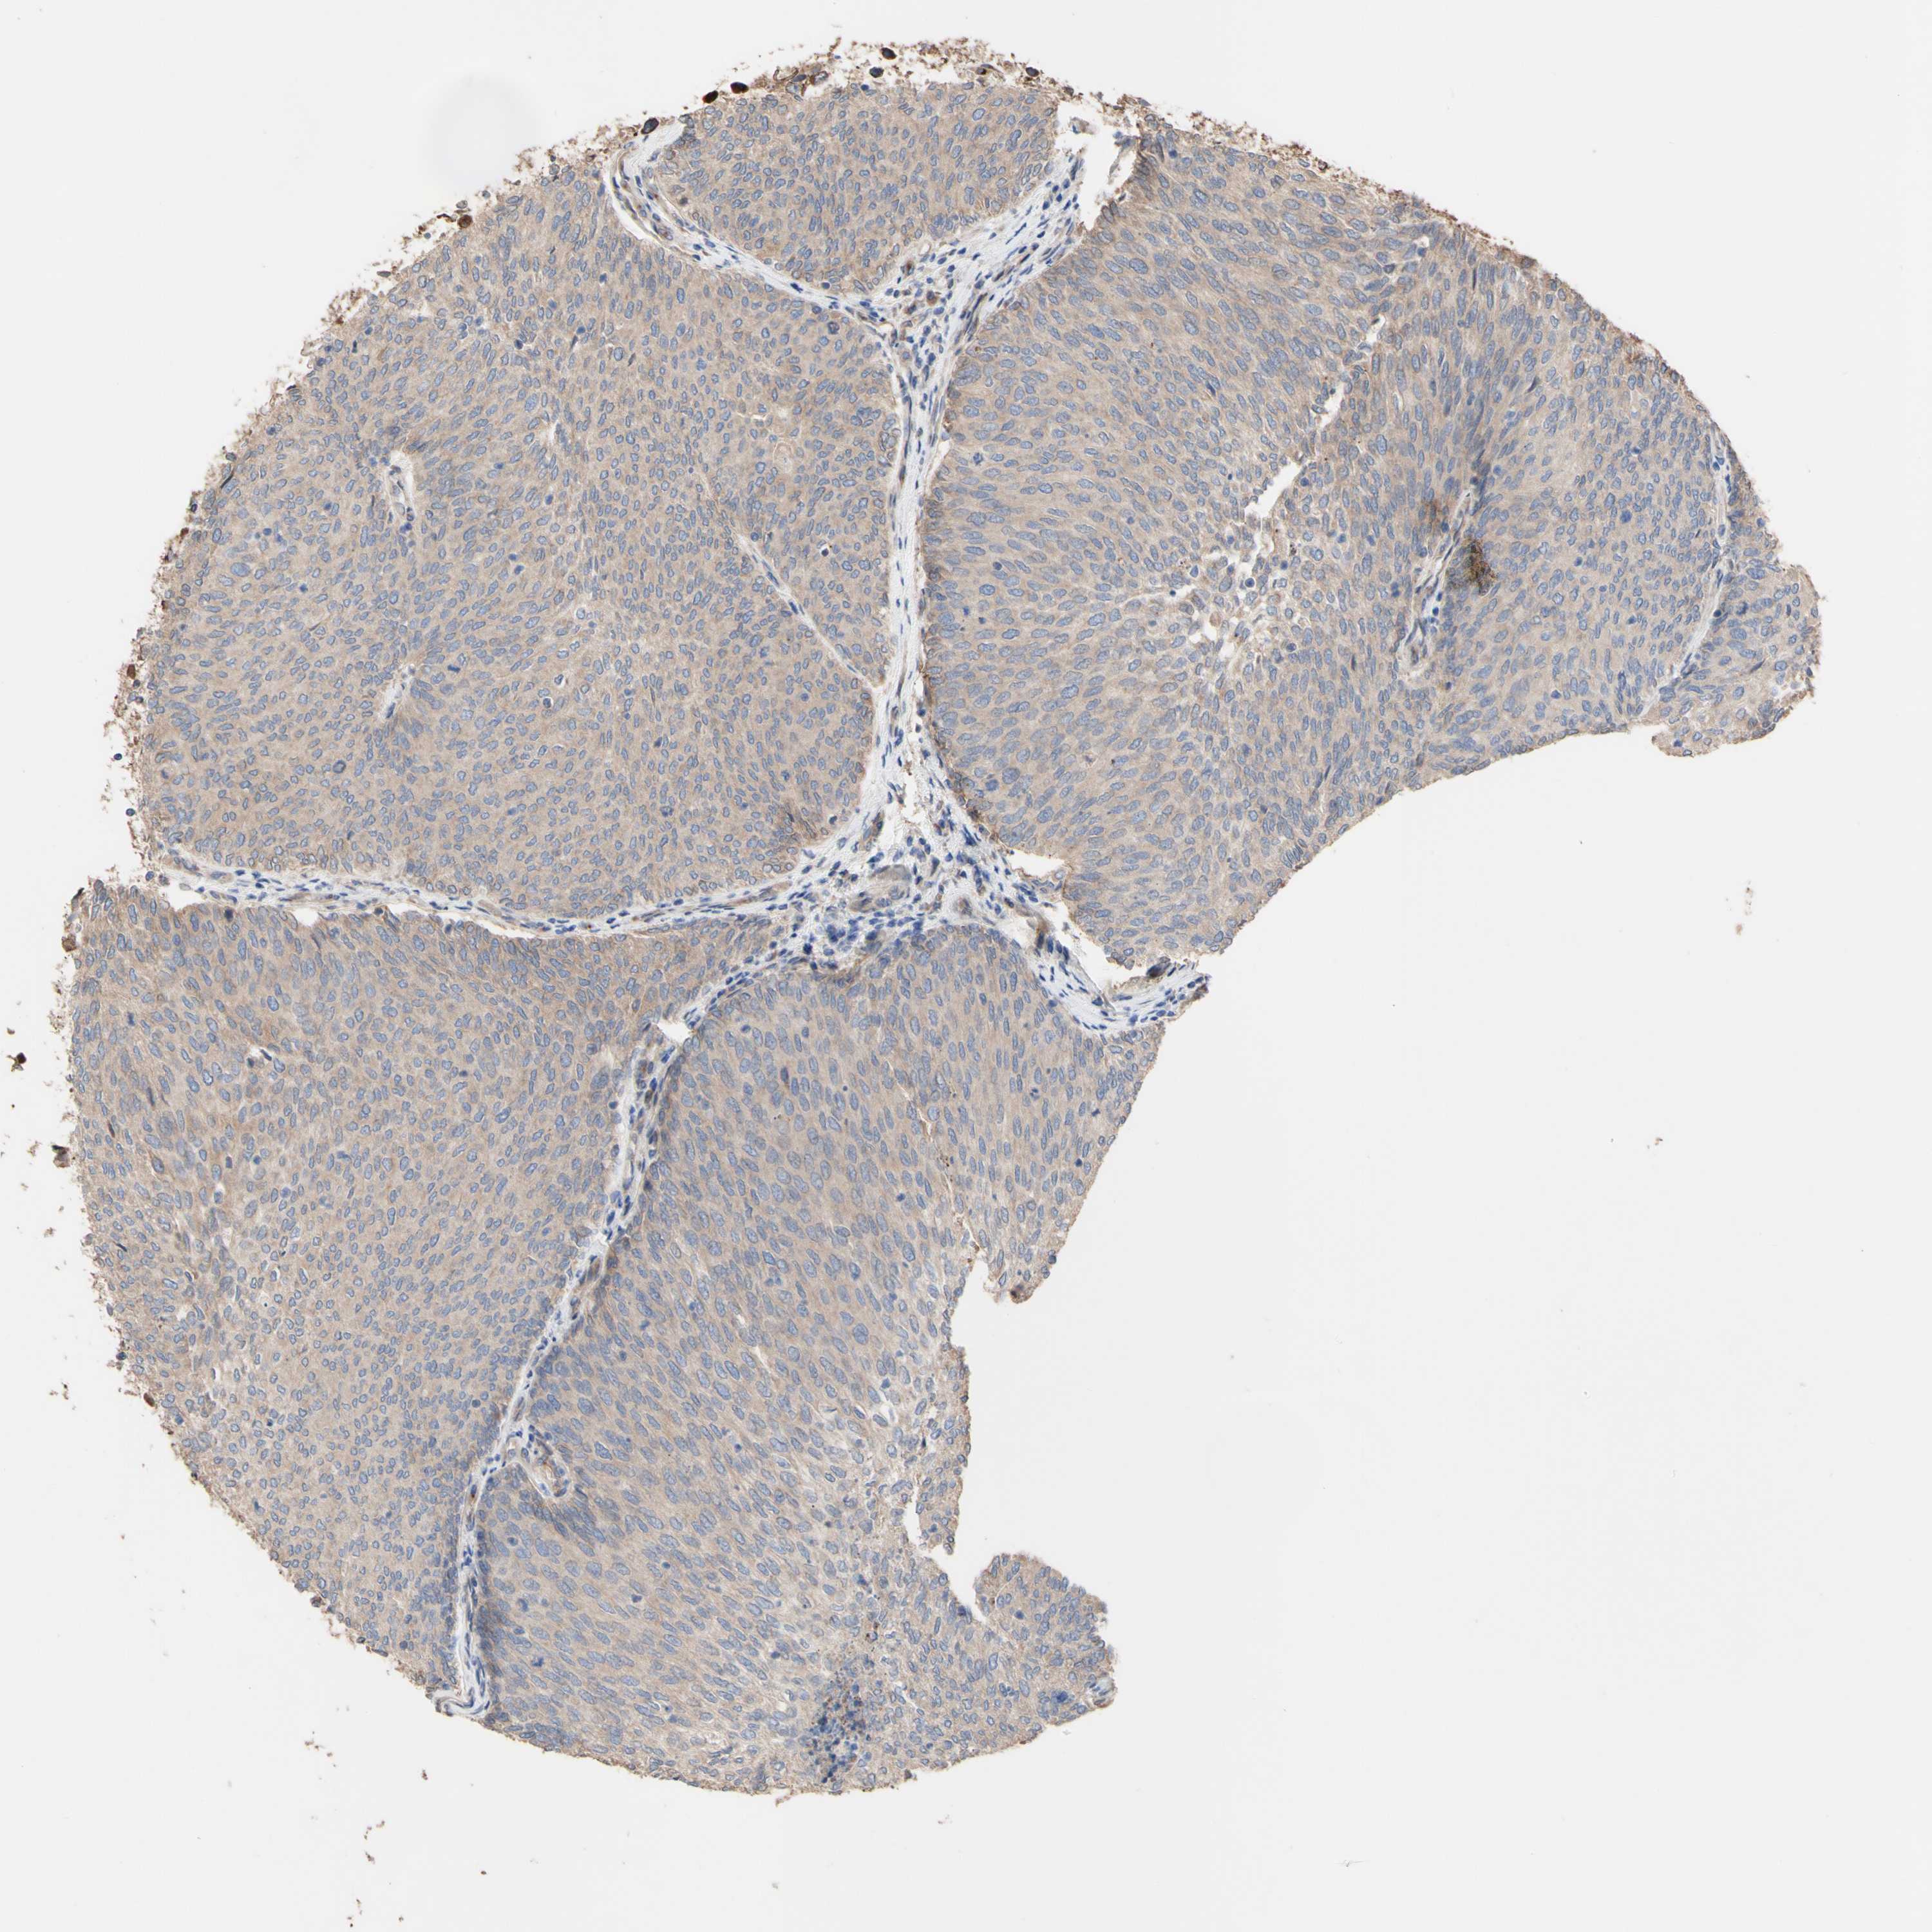

UROTHELIAL CANCER - Protein expressioni

A mouse-over function shows sample information and annotation data. Click on an image to view it in a full screen mode. Samples can be filtered based on level of antibody staining by selecting one or several of the following categories: high, medium, low and not detected. The assay and annotation is described here.

Note that samples used for immunohistochemistry by the Human Protein Atlas do not correspond to samples in the TCGA dataset.

Antibody stainingi

Antibody staining in the annotated cell types in the current human tissue is reported as not detected, low, medium, or high, based on conventional immunohistochemistry profiling in selected tissues. This score is based on the combination of the staining intensity and fraction of stained cells.

Each image is clickable and will lead to virtual microscopy that enables deeper exploration of all samples and also displays staining intensity scores, fraction scores and subcellular localization as well as patient and tissue information for each sample.

Antibody HPA011038

Antibody CAB009869

Urothelial carcinoma, Low grade

Urothelial carcinoma, High grade